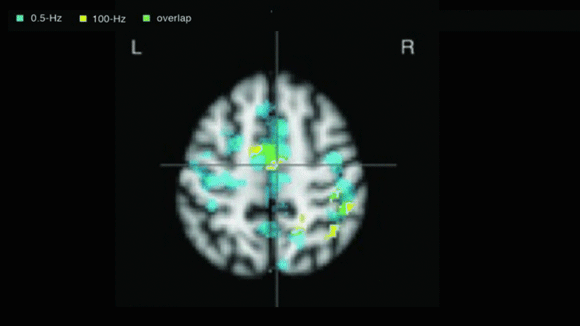

CESの信頼性は、f-MRIで確認された頭蓋神経の変化によって検証されています。CESの技術は臨床的に証明され、※FDAによって承認されています。